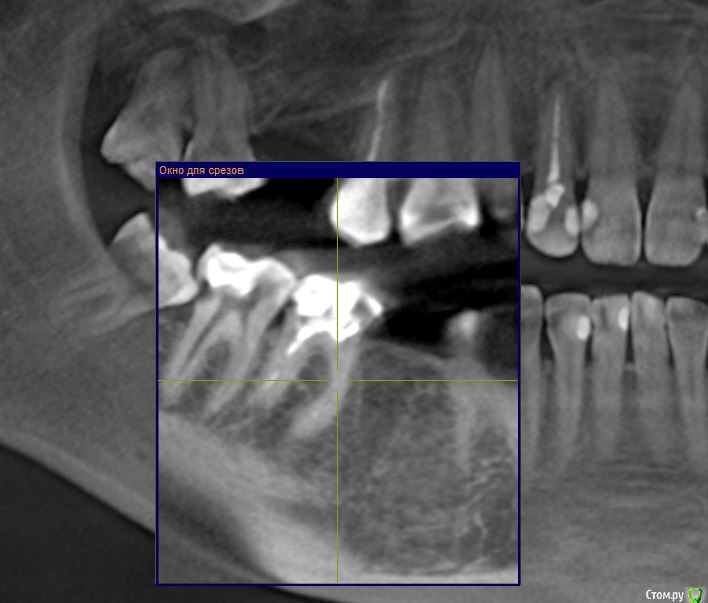

Gusenica Опубликовано 29 января, 2017 Поделиться Опубликовано 29 января, 2017 (изменено) Добрый день, уважаемые стоматологи! Прошу вас подтвердить правильность действия моих стоматологов. В частности интересует, безнадежен ли мой 36 зуб, на нем 2 кисты и я так и не поняла, почему их нельзя вылечить, но мой врач категорично настаивает на удалении. Зуб разрушен, имеет розово-серый цвет, лечился когда-то резорцином. На втором снимке киста на 22 зубе была обнаружена врачем уже после эстетического лечения, на ортопантомограмме она ее не увидела. А перелечивать мне не захотелось, при том она не настаивала, мол можно просто ее наблюдать, что она маленькая и неопасная. Так ли это? Может все же нужно лечить? И последний вопрос: зуб 46 -каналы пломбировались резорцином и сильно склерозированы. После консультации с ортопедом решили их не перелечивать, а сразу ставить на него коронку. Как вы считаете это правильное решение? Не появится ли там киста в итоге? Добавлю, что зубы с кистами никогда не беспокоили. Буду признательна за консультацию. Изменено 29 января, 2017 пользователем Gusenica Ссылка на комментарий

Доктор Добрых Дел Опубликовано 29 января, 2017 Поделиться Опубликовано 29 января, 2017 (изменено) Зуб 36 помимо кист (а точнее гранулём) имеет патологическую резорбцию корней в апикальной части поэтому перелечить его невозможно. Зуб 22 можно и наблюдать конечно, но канал недопломбирован, поэтому лучше перелечить. Зуб 46 кандидат на удаление так как судя по снимку разрушение копонковой части зуба потребует изготовления культевой вкладки, а так как каналы склерозированы их придётся рассверливать, а так как зуб резорциненый и хрупкий как стекло в будущем это с высокой ддолей вероятности приведёт к перелому корня. Я бы рекомендовал удаление 36, 46 и установку имплантатов. Перелечтвание 22. Прошу учесть, что рекомендации не являются руководством к действию. Решение принимать Вам и Вашему лечащему врачу. Изменено 29 января, 2017 пользователем Доктор Добрых Дел 1 Ссылка на комментарий